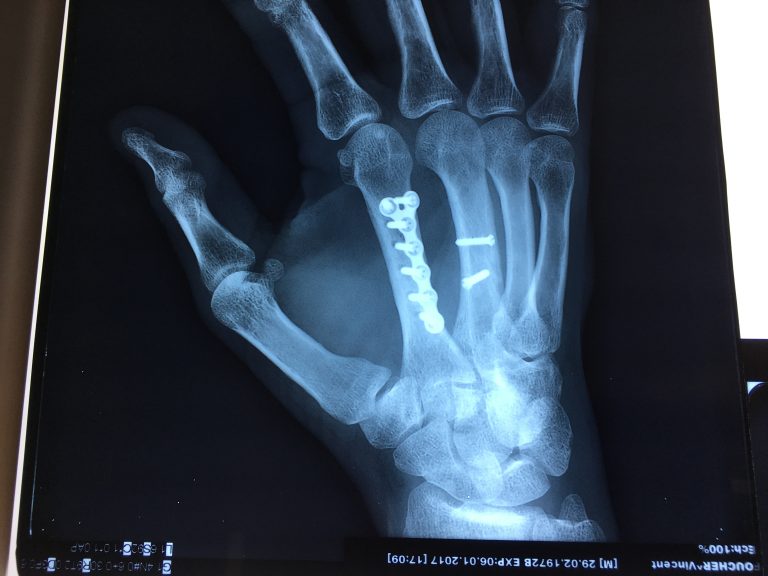

Source: liteflowyrl.pages.dev Fracturemetacarpiensplaquevis L'institut de chirurgie de la main de l'ouest parisien , L'Assurance maladie émet des recommandations concernant la durée d'arrêt de travail après une fracture de la main, et plus spécifiquement pour une fracture du métacarpe Les fractures métacarpiennes sont très fréquentes, notamment celle du 5ème métacarpien

Source: metalakeaqp.pages.dev Metacarpal Fracture Treatment Manchester Hand & Wrist Surgery , L'Assurance maladie émet des recommandations concernant la durée d'arrêt de travail après une fracture de la main, et plus spécifiquement pour une fracture du métacarpe Le diagnostic est clinique, confirmé par un bilan radiographique standard.

Source: fbilawwzp.pages.dev Metacarpal fracture causes, symptoms, diagnosis & treatment , Une douleur, un gonflement ou la déformation du dos de la main peuvent traduire une fracture du 5e métacarpien Le diagnostic est clinique, confirmé par un bilan radiographique standard.